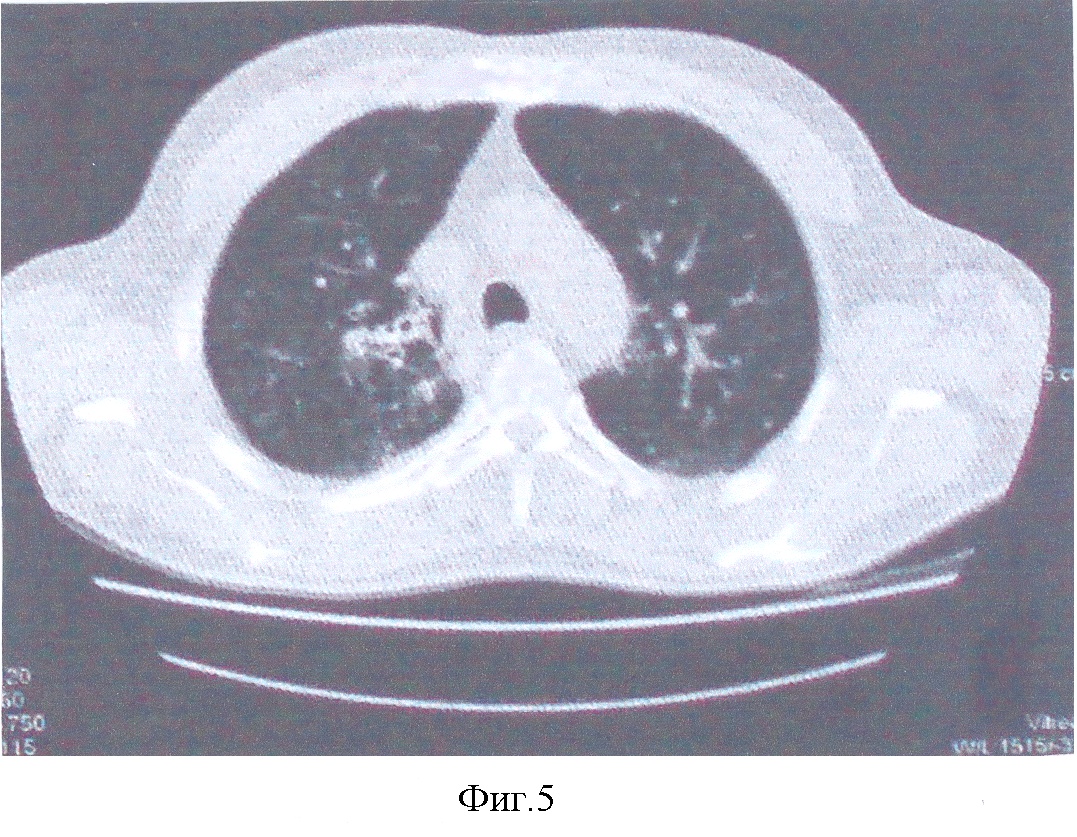

10 апреля 2006 г. больному выполнена операция Верхняя лобэктомия справа (фиг.3). Послеоперационный период протекал без осложнений. Швы сняты на 13-14 сутки. Заживление первичное. Г.а. №859952-61 от 13.04.06 г. В ткани легкого и лимфоузлах множественные эпителиоидноклеточные гранулемы с тотальным некрозом, наличием одиночных клеток типа Пирогова, в окружающей легочной ткани пневмосклероз, хроническое воспаление – продуктивная форма туберкулеза (см. фиг.5. Больной К-в. Компьютерная томограмма после проведения трех курсов АГХТ).